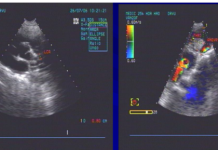

Anh ấy hút thuốc lá 1 gói/ngày trong 10 năm, tăng huyết áp phát hiện trước đây 2 năm, không có tiền sử tiểu đường và không tiền sử gia đình bệnh mạch vành. Thăm khám lúc nhập viện: Mạch:78 lần/phút, huyết áp: 130/90 mmHg, không sốt, phổi trong, tim không âm thổi, gan lách không lớn. Điện tâm đồ ST chênh xuống trong cơn đau ngực ở chuyển V4-6, men tim CKMB và HS-Troponin T tăng, siêu âm tim EF:50%, giảm động thành trước. Chúng tôi chẩn đoán: nhồi máu cơ tim không ST chênh lên. Bệnh nhân có chỉ định chụp mạch vành và tái tưới máu. Tuy nhiên, xét nghiệm máu cho thấy tiểu cầu: 1.061.000/mm3, bạch cầu: 16.800/mm3, hồng cầu và hematocrit trong giới hạn bình thường, CRP: 0.5mg/L, bệnh nhân không có dấu hiệu nhiễm trùng.

Chúng tôi tiến hành chụp mạch vành: hẹp khít 95% có hình ảnh huyết khối ở đoạn giữa động mạch liên thất trước dòng chảy TIMI 1, hẹp 40-50% nhánh mũ, thân chung trái và mạch vành phải không tổn thương. Siêu âm trong lòng mạch (IVUS) cho thấy mãng xơ vữa mềm, hình ảnh huyết khối đoạn giữa nhánh liên thất trước. Chúng tôi dùng liều nạp clopidogrel 400 mg đường uống và ức chế thụ thể GP IIbIIIa (Eptifibatide). Sau đó thủ thuật tiến hành với 1 stent không phủ thuốc Chrono 3.5/31mm vào đoạn đầu và giữa động mạch liên thất trước, tái lập dòng chảy TIMI 3, kiểm tra IVUS: stent áp tốt, mở tốt. Sau thủ thuật bệnh nhân ổn định, hết đau ngực, men tim giảm dần.

Bệnh nhân chúng tôi theo hình ảnh chụp mạch vành và siêu âm trong lòng mạch (IVUS): tổn xơ vữa vỡ tạo thành huyết khối đoạn giữa nhánh liên thất trước, chúng tôi ưu tiên lựa chọn stent không phủ thuốc vì thời gian nội mạc hóa trong stent sớm hơn so với stent phủ thuốc và giảm nguy cơ huyết khối trong stent ở bệnh nhân tăng tiểu cầu. Ngoài thuốc chống ngưng tập tiểu cầu đường uống, chúng tôi cũng sử dụng thuốc ức chế thụ thể GP IIbIIIa với mục đích giảm nguy cơ huyết khối cấp trong stent, những trường hợp lâm sàng cũng được báo cáo thành công sử dụng Ức chế thụ thể GP IIbIIIa ở bệnh nhân đặt stent mạch vành có tăng tiểu cầu (8). Gấp đôi liều clopidogrel (150mg) sau đặt stent mạch vành ở bệnh nhân hội chứng mạch vành cấp cũng được chứng minh giảm tỉ lệ huyết khối cấp trong stent trong nghiên cứu lâm sàng lớn gần đây (9).